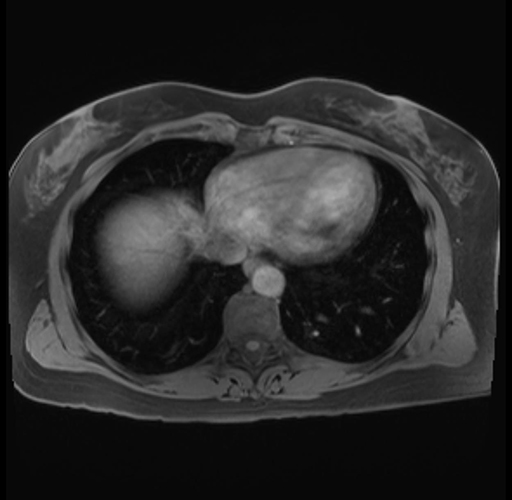

Imaging Analysis

Look through the patient's CT scan to identify any areas of concern for the necessary procedure.

Based on your CT findings, which issue(s) are present and would give reason for "planned slowing down moment(s)" in this case?